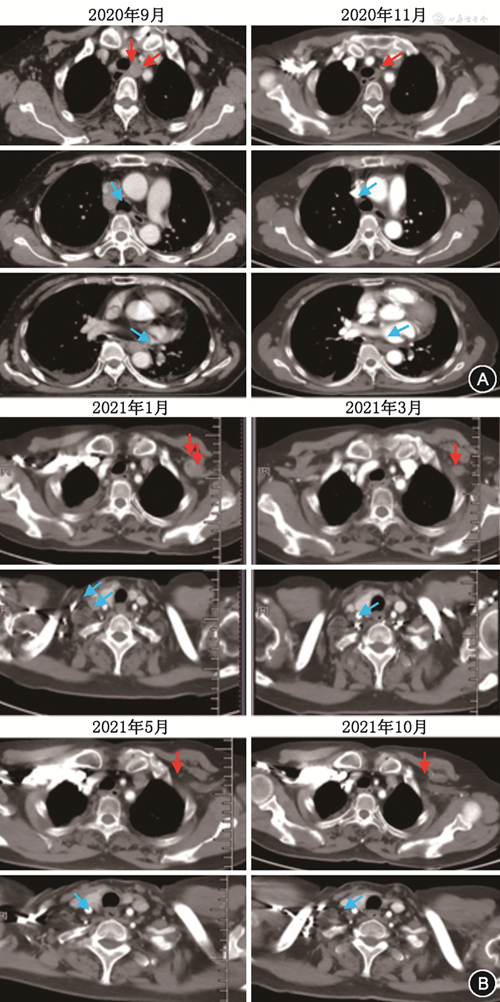

该患者“布拉格治疗”分为4个阶段:免疫激活(治疗模式:放疗+PD-1抑制剂+GM-CSF)、免疫巩固(治疗模式:PD-1抑制剂+GM-CSF)、免疫维持(治疗模式:PD-1抑制剂)、随访观察。第1、2周期分别给予纵隔(2 L)转移淋巴结大分割放疗(5 Gy照射连续3 d,每天1次),皮下注射GM-CSF(200 μg,指第4天至第17天,每天1次),静脉注射PD-1抑制剂(信迪利单抗200 mg,d4),该三联治疗方案每3周重复1次,每2个周期进行1次影像学评估,第3周和第4周期给予GM-CSF和PD-1抑制剂维持2周期;第5、6周期分别给予左腋窝转移淋巴结大分割放疗(5 Gy照射连续3 d,每天1次),并联合GM-CSF和PD-1抑制剂治疗(治疗同上),后续按治疗计划进入免疫巩固、维持、随访阶段。经过6周期“布拉格治疗”后,根据实体肿瘤反应评价标准(RECIST 1.1),该患者影像学评估为CR(图2)。此外,血清癌胚抗原(CEA)和糖类抗原125(CA125)水平降至正常范围。2022年12月患者出现双侧颈部淋巴结转移,PFS达26个月。后续该患者继续接受“布拉格治疗”2.0方案治疗[大分割放疗联合PD-1抑制剂序贯GM-CSF及白细胞介素-2(IL-2)治疗晚期难治性实体瘤的前瞻性多中心临床研究,注册号:NCT 04892498]。经1个治疗周期,患者于2023年2月1日再获评估疗效CR,截至2023年9月,该患者治疗仍在进行,疗效保持CR。治疗过程中出现了2级发热和短暂低氧血症,评估与GM-CSF治疗相关,经口服塞来昔布(200 mg,每天2次)和吸氧治疗后自行缓解。2020年11月10日被诊断为2级免疫相关性葡萄膜炎和1级甲状腺功能减退,予以小剂量糖皮质激素和甲状腺素替代治疗后恢复正常。不良事件均未明显降低患者的生活质量。